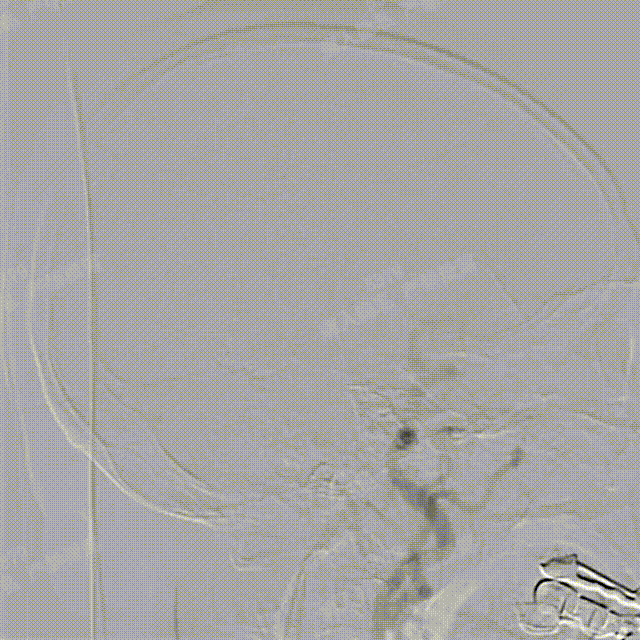

造影确认,载瘤动脉通畅、支架远端分支血流通畅、支架贴壁良好、动脉瘤内造影剂滞留。

撤出支架系统,无需后处理按摩。

正、侧位造影及术后CT复查结果观察,载瘤动脉通畅、支架贴壁良好、动脉瘤内造影剂滞留、颅内未见明显异常。